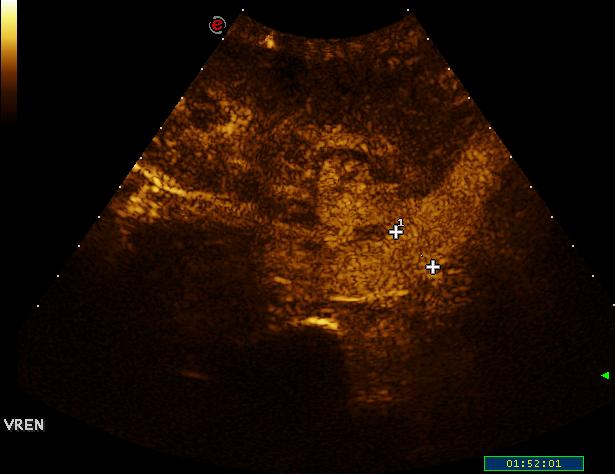

transplantált vese

v. renalis thrombosist a vizsgálat nem igazolt

- Transplant kidney